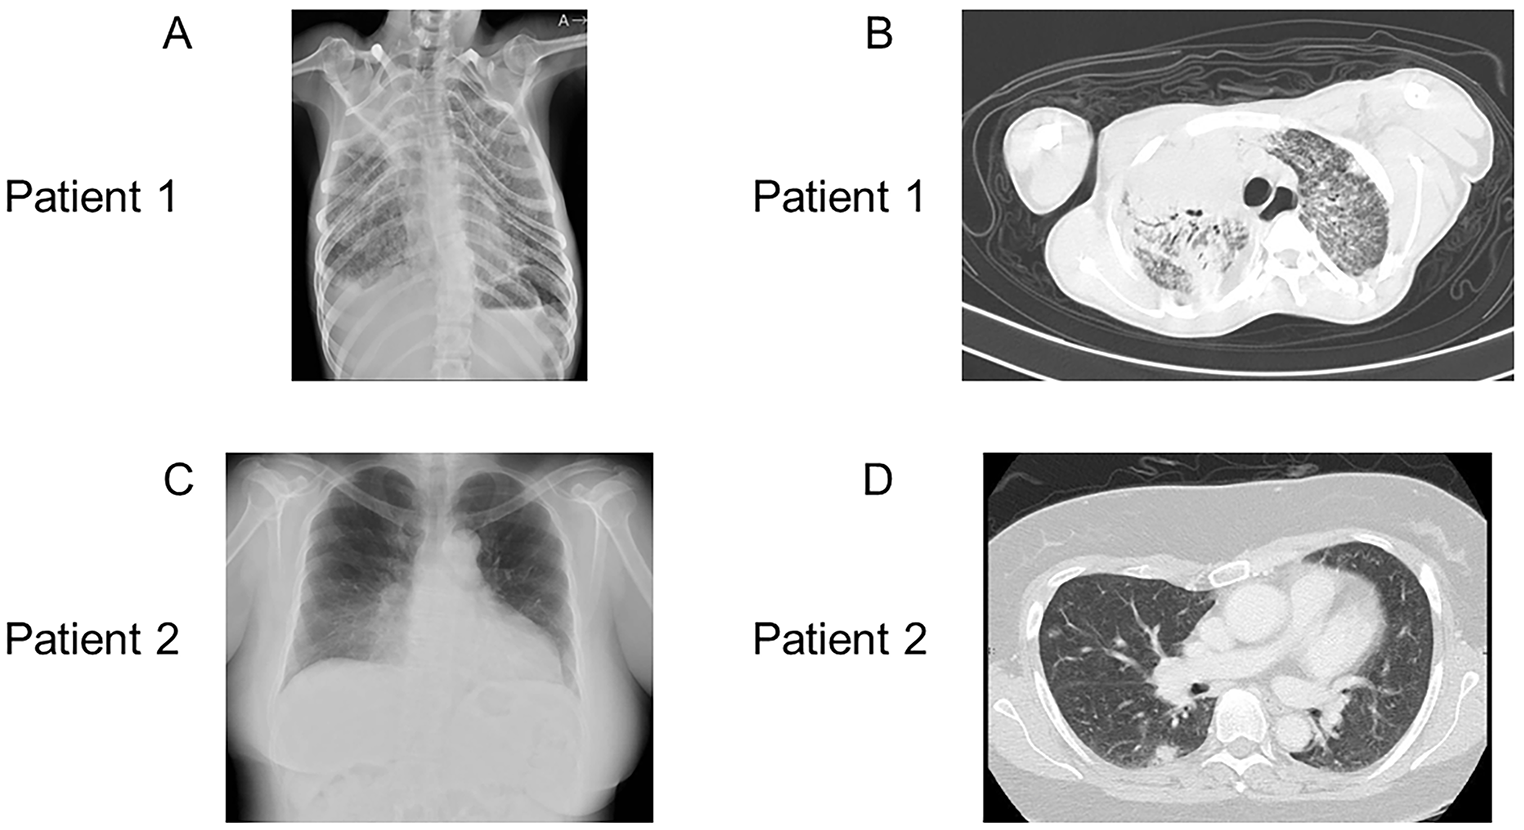

Fig. 1

Radiological findings. A: (Patient 1) Chest X-ray revealing atelectasis in the right upper lobe. The right costophrenic angle is dull, with a granular shadow in the entire lung field. B: (Patient 1) Chest CT, showing slight compression of the right upper bronchus, presence of an air bronchogram in the right upper lobe, and consolidations in the left lung, which are believed to be inflammatory changes, suggesting that the patient has pneumonia. Granular shadows are observed in the lungs. C: (Patient 2) Chest X-ray showing abnormal bilateral lung shadows. D: (Patient 2) Chest CT showing mottled frosted shadows and irregular nodular shadows in both lungs

Patient 1 was a 29-year-old male with no family history of immunodeficiency or congenital anomalies. The patient was identified as having a complex chromosomal abnormality (46, XY, 10p+, 18q−, 20p−, 21q+), and was accordingly diagnosed with chromosome 18q deletion syndrome. Subsequently, the patient developed psychomotor developmental delays, epilepsy, and scoliosis. He was admitted to the Yamabiko Medical Welfare Center, Kagoshima, Japan with severe psychomotor developmental delays at 3 years of age. After admission, the patient did not experience infections. The measles–rubella combined vaccine, Bacillus Calmette–Guérin vaccine, and other vaccines were administered, and the patient presented no severe adverse reactions. At 27 years of age, he presented with a persistent fever and cough and was diagnosed with pneumonia following chest radiography and computed tomography (CT). Although various intravenous antibiotics and micafungin were administered, they were ineffective. Three months later, his β-D-glucan was found to be high (122 pg/mL; normal, ≤ 20 pg/mL), and he was diagnosed with Pneumocystis pneumonia (PCP) based on a Pneumocystis jirovecii PCR examination of his sputum. A combination of sulfamethoxazole and trimethoprim (ST) was administered and his symptoms improved rapidly. Six months after the resolution of the first episode of pneumonia, he developed a fever and cough, his percutaneous oxygen saturation decreased, and his chest X-ray and chest CT scans showed atelectasis in the right upper lobe and a granular shadow in all the lung fields (Fig. 1A and B). The patient was diagnosed with acute pneumonia. Although his β-D-glucan, aspergillus antigen, and candida antigen levels were normal (10 pg/mL, < 0.1 UA/mL, and < 0.1 UA/mL, respectively), the patient was suspected to have fungal pneumonia. Other opportunistic infections, such as herpes zoster, persistent intestinal viral infections, and herpes viral infections, were clinically ruled out. Micafungin was administered intravenously, and the drug combination ST was administered orally, which relieved his fever and symptoms. However, owing to the recurrent opportunistic infections, we decided to evaluate the patient’s immune status. His white blood cell count was 14,700/µL, with 70% granulocytes and 22% lymphocytes (3,263/µL). His serum IgG, IgA, and IgM levels were low (188, 105, and 26 mg/dL, respectively; normal ranges: 870–1,700, 110–410, and 33–190 mg/dL, respectively). His serum IgE level was < 5 IU/mL (normal value: \(\le\)232 IU/mL). Human immunodeficiency virus (HIV) antibody test results were negative. In the analysis of lymphocyte subpopulations (Table 1), CD3+ T cells comprised 71.3% of the total lymphocytes, NK cells comprised 18.1%, and CD19+ B cells decreased to 0.72%. Although CD4+ T cells were within the normal range, naïve CD4+ T cells were depleted, accounting for only 3.58% of the CD3+CD4+ cell population. The naïve CD8+T cells were within normal ranges. T-cell receptor (TCR)Vβ repertoire analysis revealed prominent skewing to Vβ16 for the CD4+ T cells (Fig. 2A). In the lymphocyte stimulation test, proliferation in response to both phytohemagglutinin (PHA) stimulation and concanavalin A was low (8,226 cpm; normal value: 20,500–56,800 cpm and 8,053 cpm; normal value: 20,300–65,700 cpm, respectively). The level of T-cell receptor recombination excision circles (TREC) was extremely low (25.27 copies/105 cells, normal > 565 copies/105 cells). Additionally, the Ig κ-deleting recombination excision circle (KREC) level was extremely low (93.36 copies/105 cells; normal, ≥ 456 copies/105 cells). The carboxyfluorescein diacetate succinimidyl ester (CFSE) cell proliferation test showed that the CD4+ and CD8+ T cells failed to divide in response to PHA (Fig. 3). T-cell proliferation studies were performed when the patient was not experiencing acute illness. Based on these findings, the patient was diagnosed with LOCID, a combination of humoral and cell-mediated immunodeficiencies. 18q deletion was confirmed through array-based comparative genomic hybridization (CGH) analysis, and presented with a loss of 18q21.32–q22.3 in the patient (Fig. 4A and Supplementary Table 1). The patient exhibited no morbid variants in his normal alleles without deletion of 18q in the whole-exome analyses. Subsequently, immunoglobulins were substituted periodically, and ST was administered prophylactically. However, the patient died of fungal pneumonia 2 years after the first episode.

Patient 2 was a 48-year-old female who was referred to the Tokyo Medical and Dental University Hospital, Tokyo, Japan with abnormal bilateral lung shadows, found during chest radiography at a routine annual checkup (Fig. 1C). She experienced intellectual disability, bilateral foot deformities, and bilateral third finger morphological abnormalities. She had been attending Tokyo Medical and Dental University Hospital because of hearing loss, congenital stenosis of the external auditory canal, and cleft lip and palate. Regarding her family history, no immune deficiencies or congenital anomalies were found. Chest CT revealed mottled frosted shadows and irregular nodular shadows in both lungs (Fig. 1D), as well as enlarged left supraclavicular fossa, bilateral axillae, mediastinum, abdominal cavity, and inguinal lymph nodes. A left inguinal lymph node biopsy was performed to differentiate lymphoproliferative diseases such as lymphoma. Consequently, the patient was diagnosed with granulomatous lymphadenitis and was followed up without treatment. G-banding of the biopsied lymph nodes revealed a chromosome 18 long-arm defect. The deletion was located at q21 on chromosome 18. Therefore, the patient was diagnosed with chromosome 18q deletion syndrome. Her white blood cell count was 5,100/µL, with 69% granulocytes and 21% lymphocytes (1,071 /µL). Her serum IgG, IgA, and IgM levels were low (8, 9, and 131 mg/dL, respectively). Her serum IgE level was 0.3 IU/mL, and her human immunodeficiency virus antibody test results were negative. Analysis of the lymphocyte subpopulations (Table 1) indicated that CD3+ T, NK, and CD19+ B cells comprised 61.5, 22.6, and 9.22% of the total lymphocytes, respectively. CD4+ T-cell levels were decreased to 396/µL. Furthermore, the naïve CD4+ T cells were depleted, accounting for only 5.97% of the CD3+CD4+ cell population. CD8+ T-cell levels were decreased to 217/µL, and naïve CD8+ T cells were depleted to 15.0% of the CD3+CD8+ cell population. Among the CD19+B cells, the proportion of IgDCD27+ (class-switched memory) B cells was extremely low (1.17% of CD19+ cells). TCRVβ repertoire analysis showed prominent skewing to Vβ13.2 for the CD8+ T cells (Fig. 2B). The levels of TREC were extremely low (0 copies/105 cells). Additionally, the KREC level was extremely low (11.4 copies/105 cells). The CFSE T-cell proliferation assay performed after the acute phase indicated that the CD4+ and CD8+ T cells did not divide in response to PHA stimulation (Fig. 3). Based on these findings, patient 2 was diagnosed with LOCID. 18q deletion was confirmed by array-based CGH analysis, and presented with a loss of 18q21.33–qter in the patient (Fig. 4B and Supplementary Table 2). Analysis of the targeted panel sequence for 400 genes related to inborn errors of immunity (IEI) using DNA from peripheral blood mononuclear cells indicated that the patient did not exhibit any morbid variants in her normal alleles (without deletion of 18q). Immunoglobulin replacement therapy and prophylactic ST were subsequently initiated.